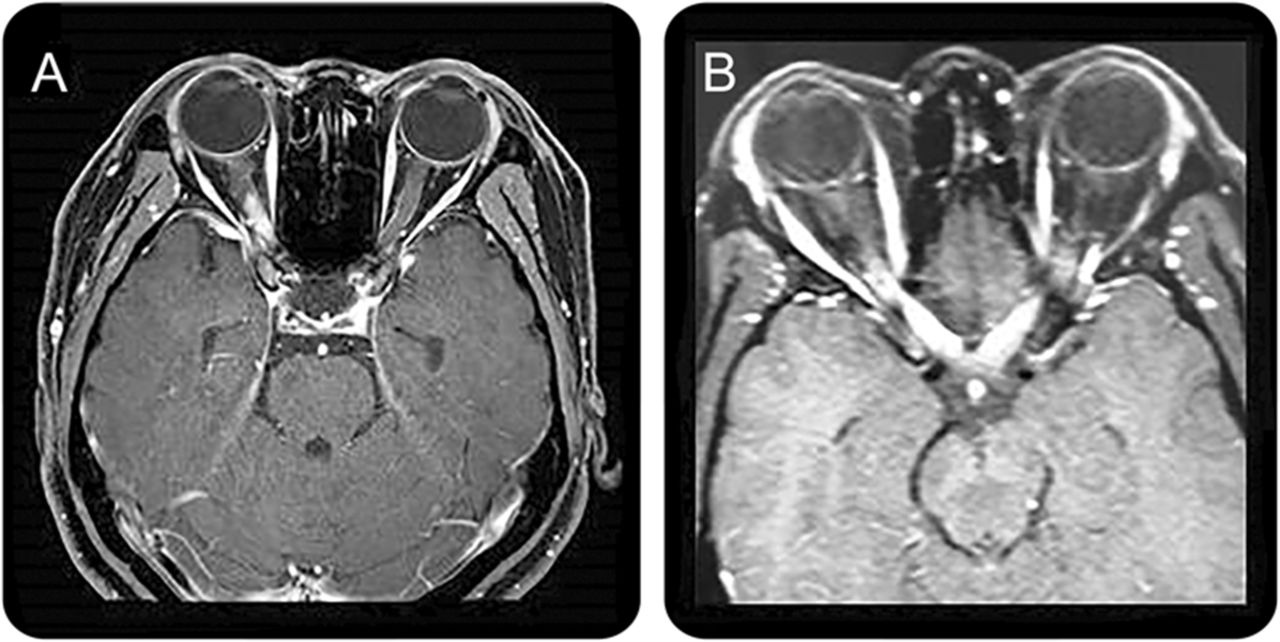

核磁共振成像研究已经报道特异性的视神经鞘增厚,视神经hyperintensities t2加权序列和钆增强在t1序列在急性NMOSD。14,17然而,类似的结果也一直在中描述的女士,e22这些发现并不认为是NMOSD的诊断。最近的研究观察之间的微分视神经病变的MRI特征和NMOSD女士。32,33趋势更多的后参与视神经交叉等,同时两国疾病,一直在观察NMOSD (图3)。32,33因此,长段视神经的炎症,特别是当同时双边和后方延伸到视交叉,应该让我们怀疑NMOSD在适当的临床的诊断上下文。